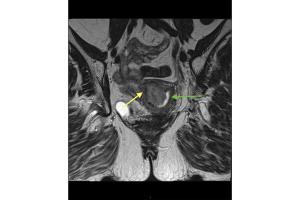

These ten images can help ob/gyns recognize the additional information GBCA administration provides in MRIs.

Gadolinium-based intravenous contrast agents (GBCA) provide additional information based on signal intensity changes after GBCA administration.

Concerns have been raised about the safety of GBCA. Experts review the latest data to support counseling of patients who may have repeated exposure.